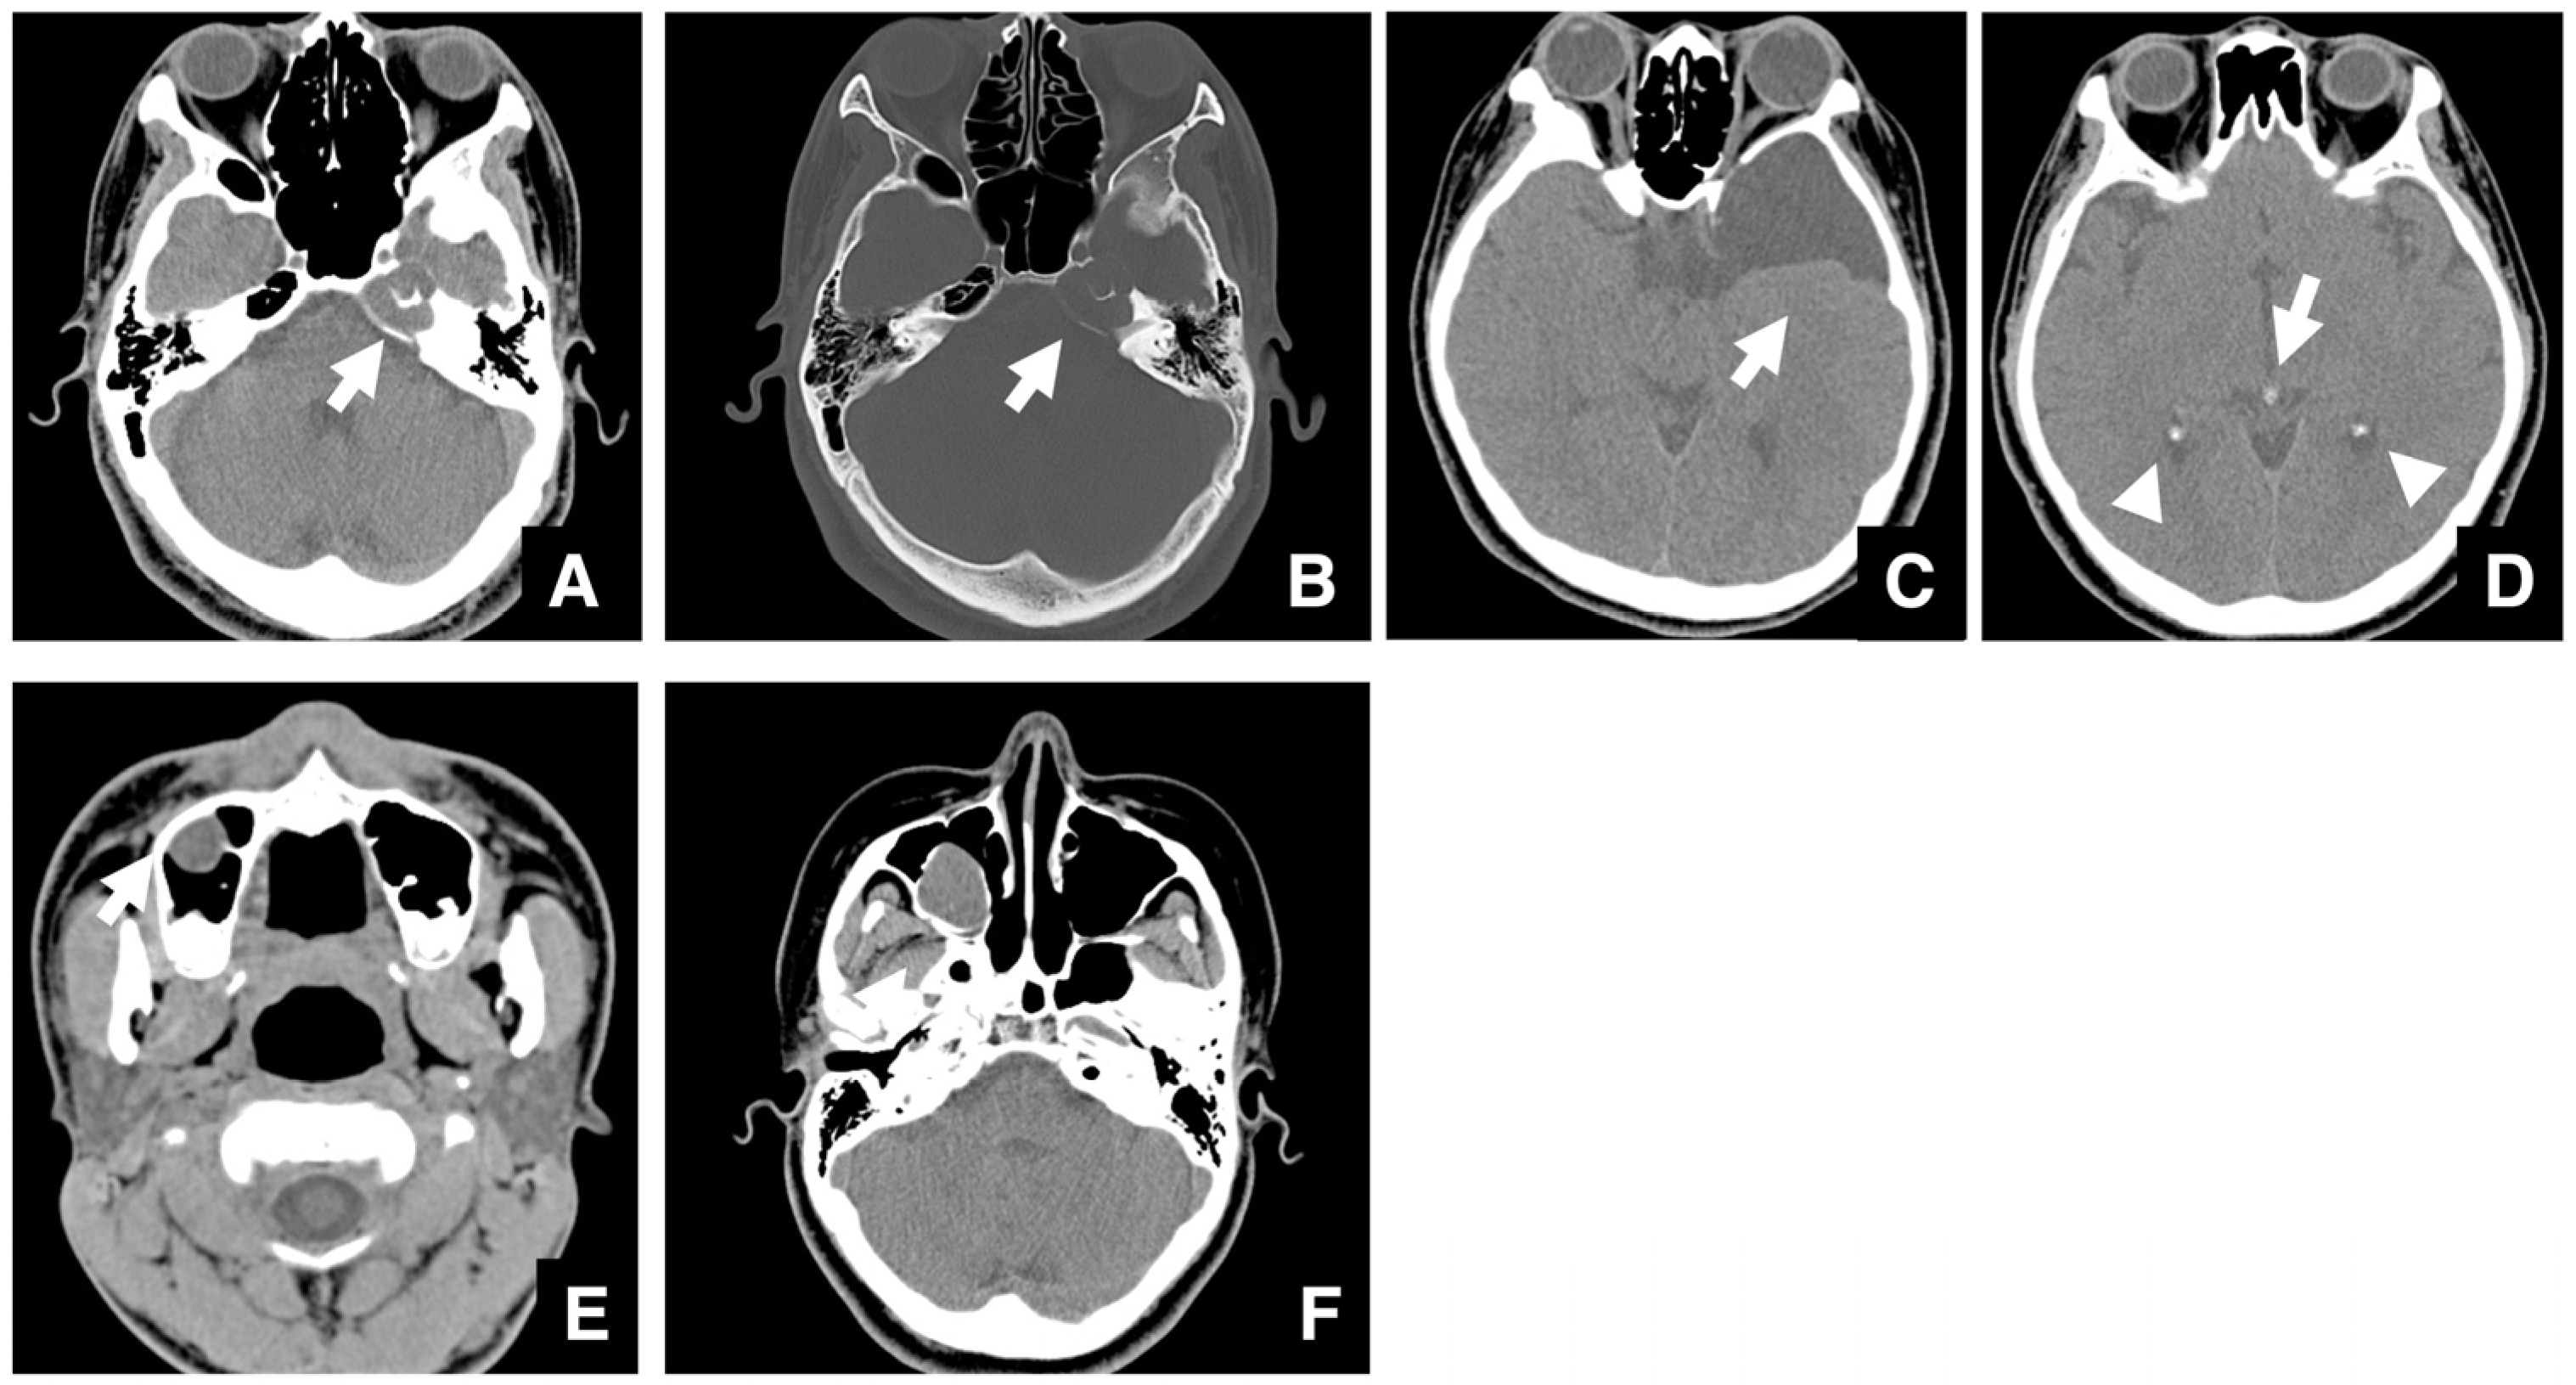

| Setting the osteotomy line 1. Evaluation of the position of the mandibular canal and surrounding bone quality Presence or absence of mandibular canal bifurcation and course of resection site Distance from the buccal wall of the mandibular canal to the buccal cortical bone margin Bone quality around the mandibular canal (CT number) 2. Distance from the mandibular notch to the lingula Whether it is 14 mm or more 3. Morphology of the mandible and variation in cortical bone thickness Cortical bone thickness in the medial osteotomy area and lateral osteotomy area Enhanced safety through improved visibility 1. Medial curvature of the mandibular ramus Mandibular ramus is straight or strong curvature 2. Course of small blood vessels along the bone surface Depression of the buccal-lingual cortical bone from the mandibular fossa to the mandibular ramus region, trabecular bone defect Improved success rates through enhanced postoperative bone integration 1. Degree of interference between bone segments The presence or absence of interference between the proximal and distal bone segments formed during virtual mandibular deformity surgery |

| Improving safety through prediction of surgical difficulty and complication 1. Circumstance of pterygoid venous plexus Carefully observe the fat tissue surrounding the medial and lateral pterygoid muscles to assess the development of the internal vascular structures (using CT and MR to evaluate the size of the fat tissue) 2. Fusion status of the maxillary tuberosity and pterygomaxillary suture When the fusion is narrow and the degree of calcification (CT number) is low or when the fusion is wide and high 3. Course of the descending palatine artery and thickness of surrounding bone When the palatal canal wall is thick, the probability of damage during transection is low. When it is thin, the possibility of damage cannot be ruled out. Setting the osteotomy line 1. Distance from the piriform rim to the greater palatine canal Long, short, cortical bone thickness, presence or absence of bone irregularities 2. Evaluation of the size, morphology, and internal features (mucosa, septa, etc.) of the maxillary sinus Size, shape, presence or absence of septa, presence or absence of masses, presence or absence of mucosal thickening 3. Relationship between the floor of the maxillary sinus and the apices of the molars Describe the maxillary sinus floor and the apex of each molar tooth 4. Presence of nasal septal deviation, size of the nasal passages, and thickness of the lateral nasal wall bone Presence or absence of nasal septal deviation, Size of the nasal passage, Thickness of the cortical bone of the lateral wall 5. Course of the mandibular artery The course from the pterygoid cleft to the pterygopalatine fossa in the posterior maxilla |